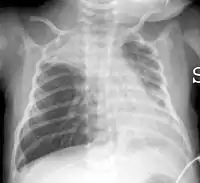

![]() Типові двобічні затемнення на рентгенограмі органів грудної клітки у дитини з тяжким перебігом респіраторно-синцитіальної інфекції Типові двобічні затемнення на рентгенограмі органів грудної клітки у дитини з тяжким перебігом респіраторно-синцитіальної інфекції | |